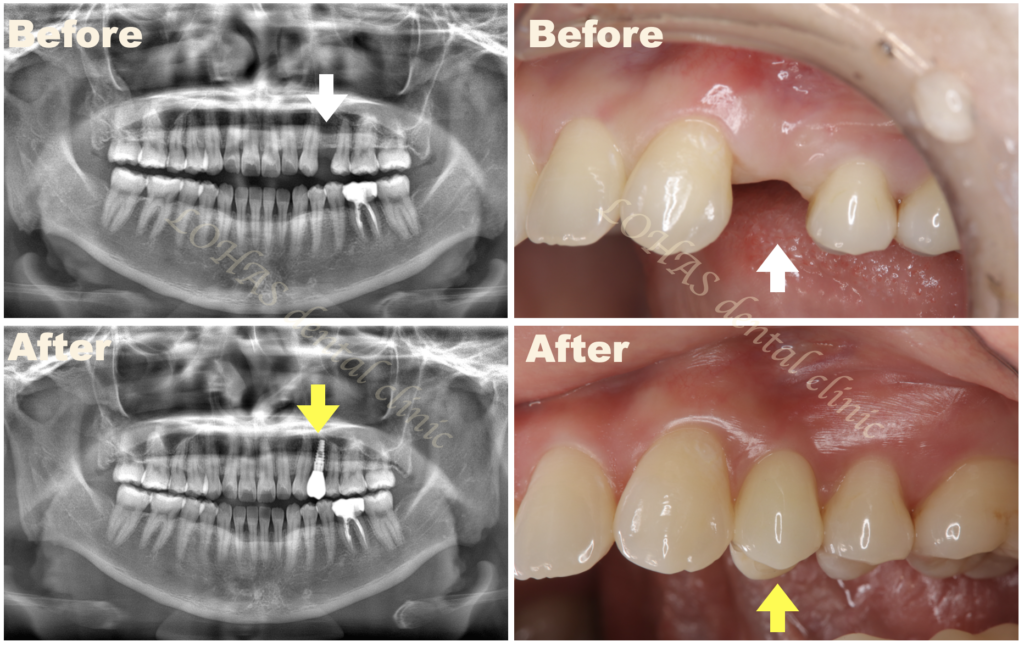

インプラント埋入と同時に仮歯が入る「インプラント即時プロビジョナル」を行なった患者様【30代・女性】

左上の第一乳臼歯が残っていたようですが、すでに脱落してしまっており、歯がない状態でした。

幸い乳歯の残っていた部分には十分な骨の高さと、厚み、また歯肉の状態も良かったので、インプラント埋入と同時に仮歯を入れる治療プランをご提案しました。

患者様はインプラント当日に歯が入り、隣の歯を削るなどをしなくて良いのであれば理想的な治療だと喜んでくださり、「インプラント埋入と即時プロビジョナルレストレーション(仮歯)」の治療方針で進めることにしました。

インプラントをした日に仮歯まで入れることができ、その後問題がなければ、最後のセラミックの型取りをしてセットすれば治療を終えることができるので、治療に必要な通院回数はとても減らすことができました。

手術直後はあまり強く咬合力が加わらないように短い歯にしていますが、きちんと骨接合したのちには天然の歯と同じような形態に変更し、最終的には天然の歯と見分けがつかないようなセラミックの歯を入れることができました。

インプラント周囲には健康な骨と歯茎が必須になるので、非常に自然な仕上がりに、患者様もとても喜んでくだいました。